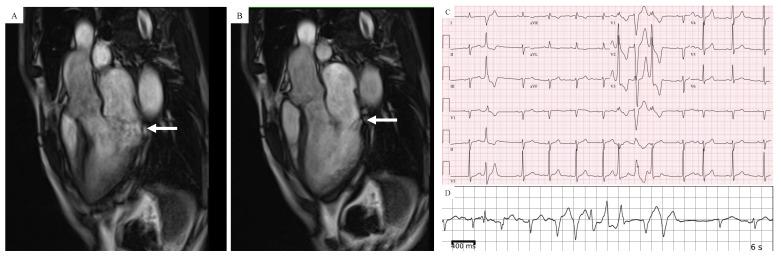

Sudden cardiac death (SCD) from ventricular fibrillation (VF) can occur in mitral valve prolapse (MVP) in the absence of other comorbidities including mitral regurgitation, heart failure or coronary disease. Although only a small proportion with MVP are at risk, it can affect young, otherwise healthy adults, most commonly premenopausal women, often as the first presentation of MVP. In this review, we discuss arrhythmic mechanisms in MVP and mechanistic approaches for sudden death risk assessment and prevention. We define arrhythmogenic or arrhythmic MVP (AMVP) as MVP associated with complex and frequent ventricular ectopy, and malignant MVP (MMVP) as MVP with high risk of SCD. Factors predisposing to AMVP are myxomatous, bileaflet MVP and mitral annular disjunction (MAD). Data from autopsy, cardiac imaging and electrophysiological studies suggest that ectopy in AMVP is due to inflammation, fibrosis and scarring within the left ventricular (LV) base, LV papillary muscles and Purkinje tissue. Postulated mechanisms include repetitive injury to these regions from systolic papillary muscle stretch and abrupt mitral annular dysmotility (excursion and curling) and diastolic endocardial interaction of redundant mitral leaflets and chordae. Whereas AMVP is seen relatively commonly (up to 30%) in those with MVP, MVP-related SCD is rare (2-4%). However, the proportion at risk (i.e., with MMVP) is unknown. The clustering of cardiac morphological and electrophysiological characteristics similar to AMVP in otherwise idiopathic SCD suggests that MMVP arises when specific arrhythmia modulators allow for VF initiation and perpetuation through action potential prolongation, repolarization heterogeneity and Purkinje triggering. Adequately powered prospective studies are needed to assess strategies for identifying MMVP and the primary prevention of SCD, including ICD implantation, sympathetic modulation and early surgical mitral valve repair. Given the low event rate, a collaborative multicenter approach is essential.

在没有二尖瓣反流、心力衰竭或冠心病等其他合并症的情况下,二尖瓣脱垂(MVP)患者可能会发生心室颤动(VF)导致的心脏性猝死(SCD)。虽然只有一小部分MVP患者有风险,但它可影响年轻的、其他方面健康的成年人,最常见的是绝经前女性,且常常是MVP的首发表现。在本综述中,我们讨论了MVP的心律失常机制以及猝死风险评估和预防的机制性方法。我们将致心律失常性或心律失常性MVP(AMVP)定义为与复杂且频发的室性早搏相关的MVP,将恶性MVP(MMVP)定义为具有SCD高风险的MVP。易患AMVP的因素包括黏液瘤样、双叶MVP和二尖瓣环分离(MAD)。尸检、心脏成像和电生理研究数据表明,AMVP中的早搏是由于左心室(LV)基部、LV乳头肌和浦肯野组织内的炎症、纤维化和瘢痕形成所致。推测的机制包括收缩期乳头肌拉伸以及二尖瓣环突然运动障碍(偏移和卷曲)对这些区域的反复损伤,以及冗余二尖瓣叶和腱索的舒张期心内膜相互作用。虽然AMVP在MVP患者中相对常见(高达30%),但与MVP相关的SCD很少见(2 - 4%)。然而,有风险的比例(即患有MMVP的比例)尚不清楚。在其他方面为特发性SCD的患者中,心脏形态和电生理特征与AMVP相似的聚集现象表明,当特定的心律失常调节因子通过动作电位延长、复极异质性和浦肯野触发导致VF起始和持续时,MMVP就会出现。需要有足够样本量的前瞻性研究来评估识别MMVP和SCD一级预防的策略,包括植入式心律转复除颤器(ICD)植入、交感神经调节和早期二尖瓣手术修复。鉴于事件发生率较低,多中心协作方法至关重要。